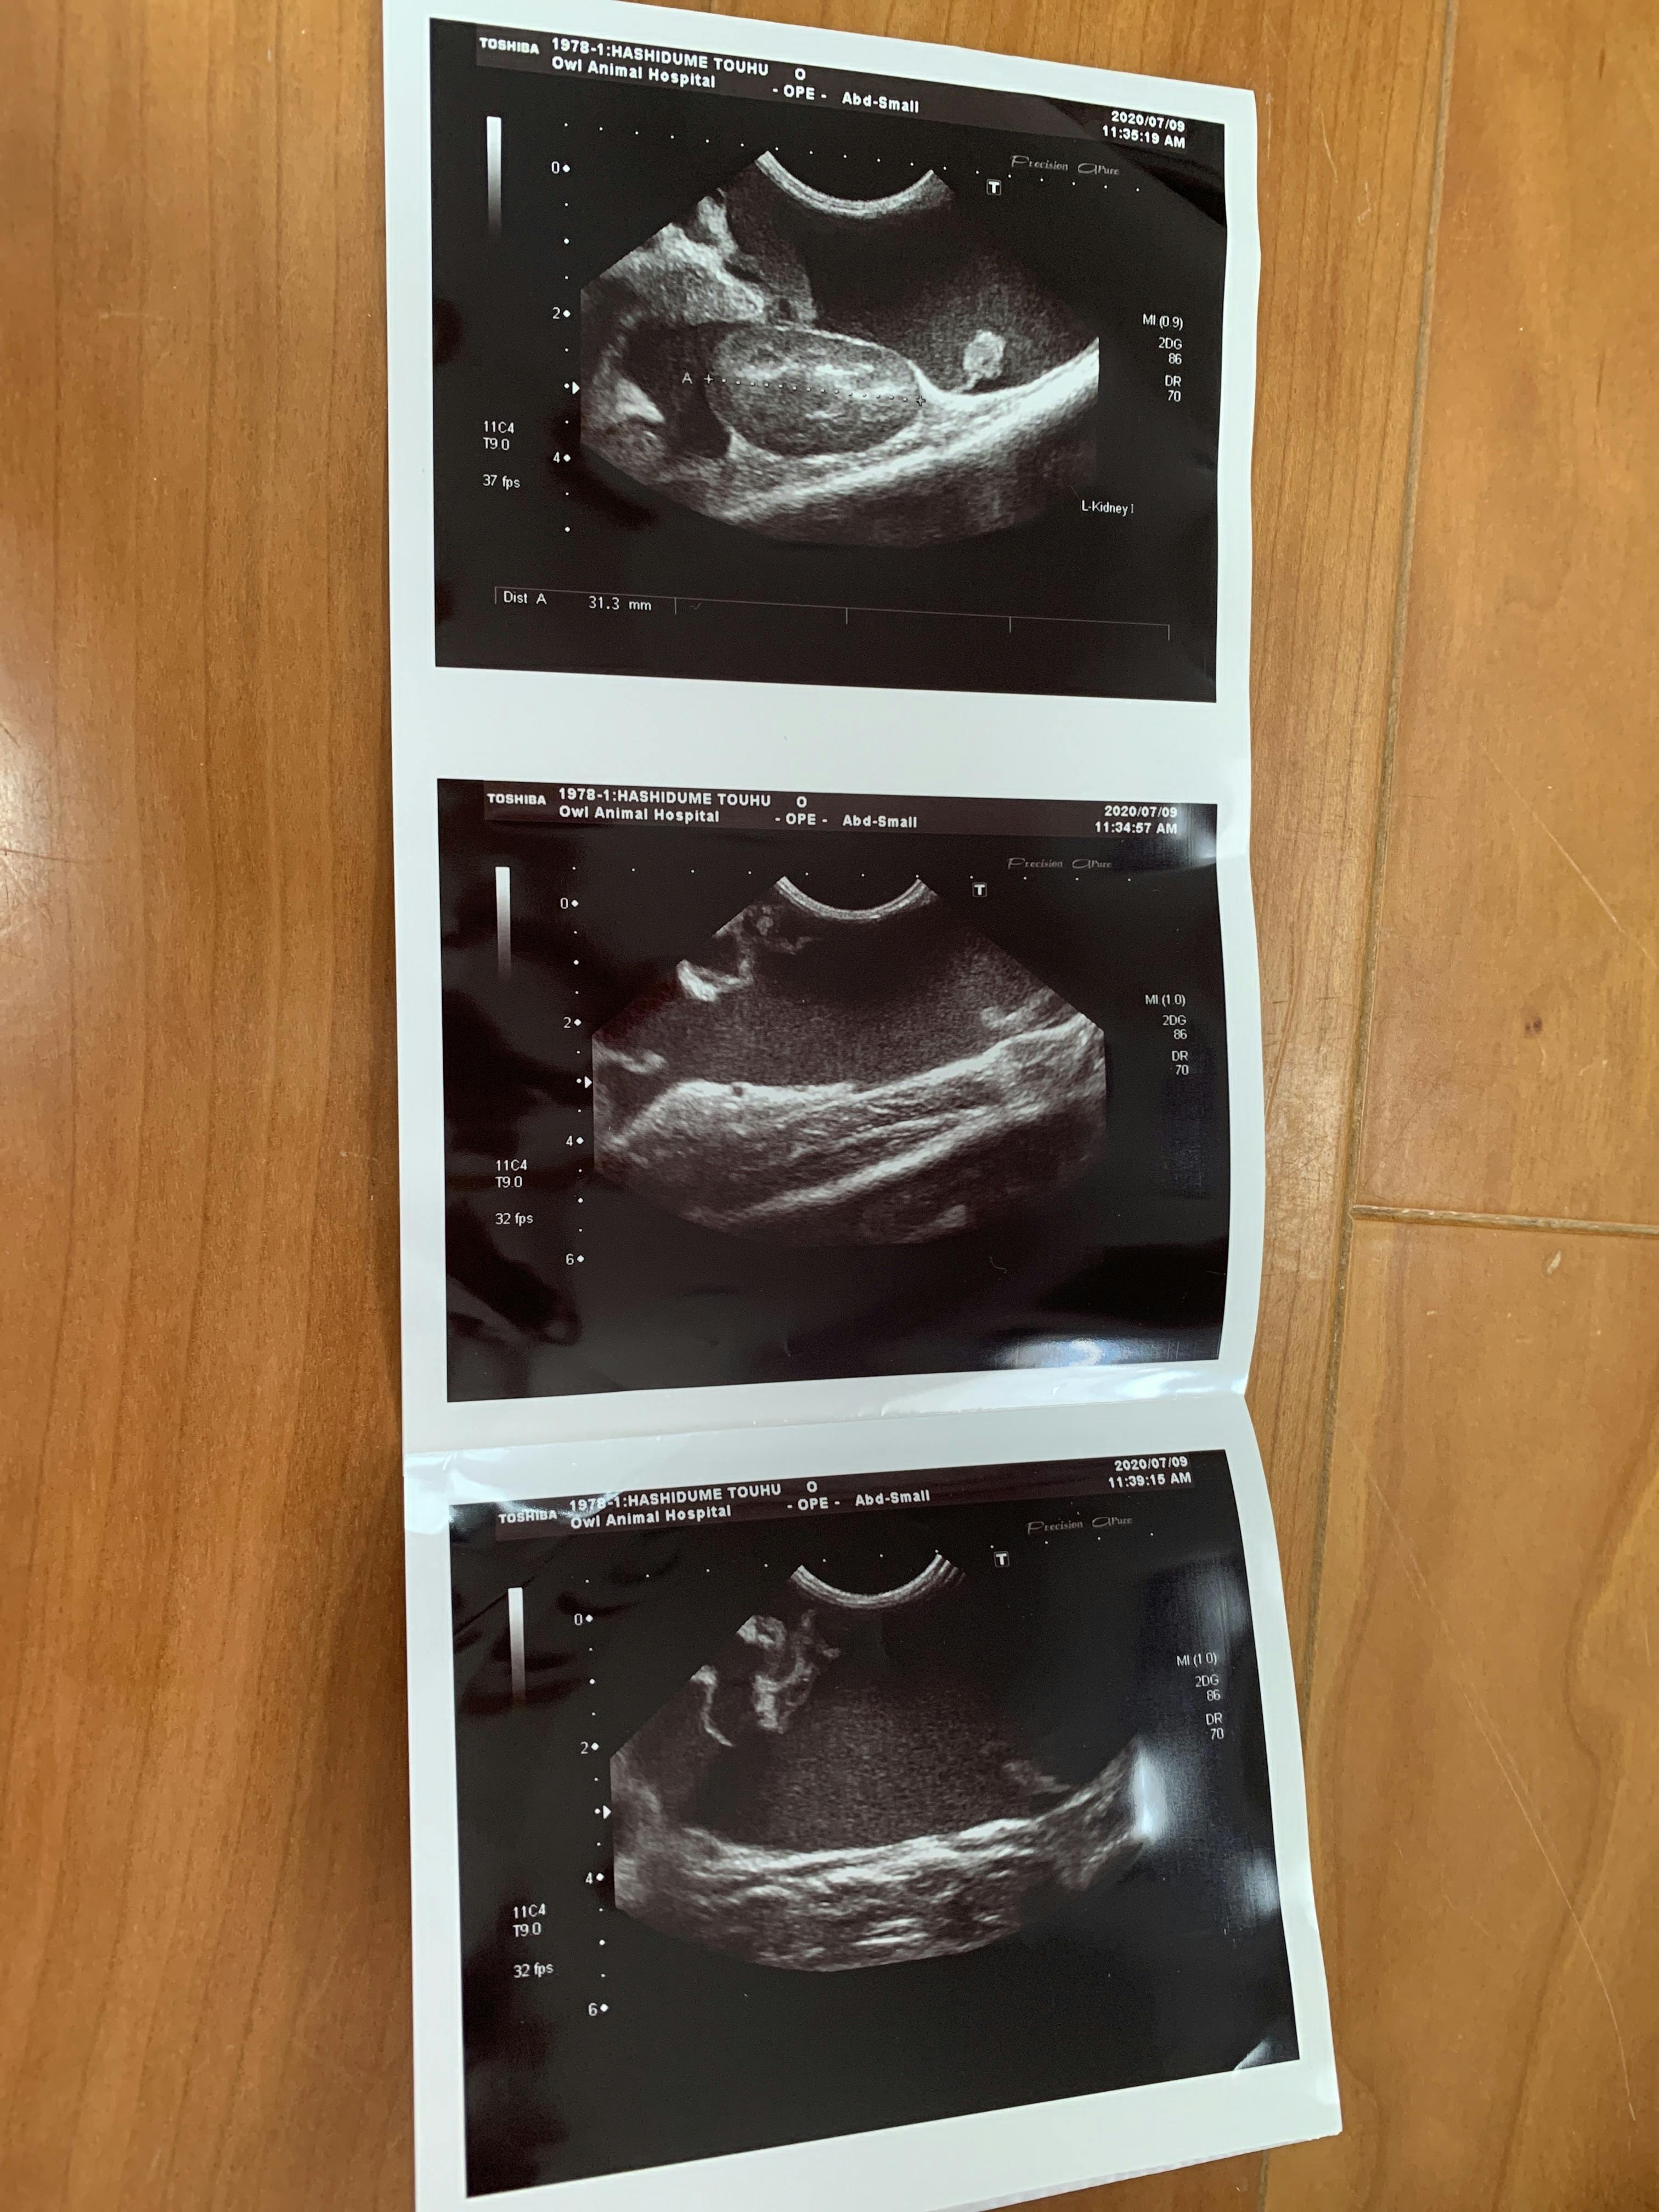

7月9日 朝から病院に連れて行きました。血液検査とエコーの結果

ここで初めて猫伝染性腹膜炎かも知れないと言われました。少しお腹が膨らんでいるのは便秘ではなく腹水でした。私は初めてその病名を聞きました。先生が言うには、このFIP と言う病気は進行が早く数日〜2か月で亡くなる怖い怖い病気ですとの事でした。その後の先生の話を涙が流れるのを必死にこらえて聞いていました。

とうふちゃんの場合 腹水があるので、腹水を外部の検査に出し結果が出るまで5日間くらいかかりますが、検査結果が出てから、また考えていきましょう ただ、その病気だと助かる見込みはないです との事でした。周りに誰も居ない帰りの車では大人げないですが、わんわん泣いてしまいました。とうふと私の帰りを待っていた息子に病院での事を伝えると息子もポロポロ涙を流してとうふを優しく撫でていました。

ますます腹水が増えてきています